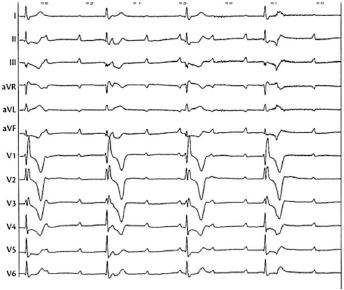

Um senhor de 68 anos com BRE prévio foi submetido a um EEF devido à síncope. Durante o posicionamento de um cateter no ventrículo direito, houve assistolia de 4s, com retorno a ritmo próprio, como mostrado na figura a seguir.

Figura 1: